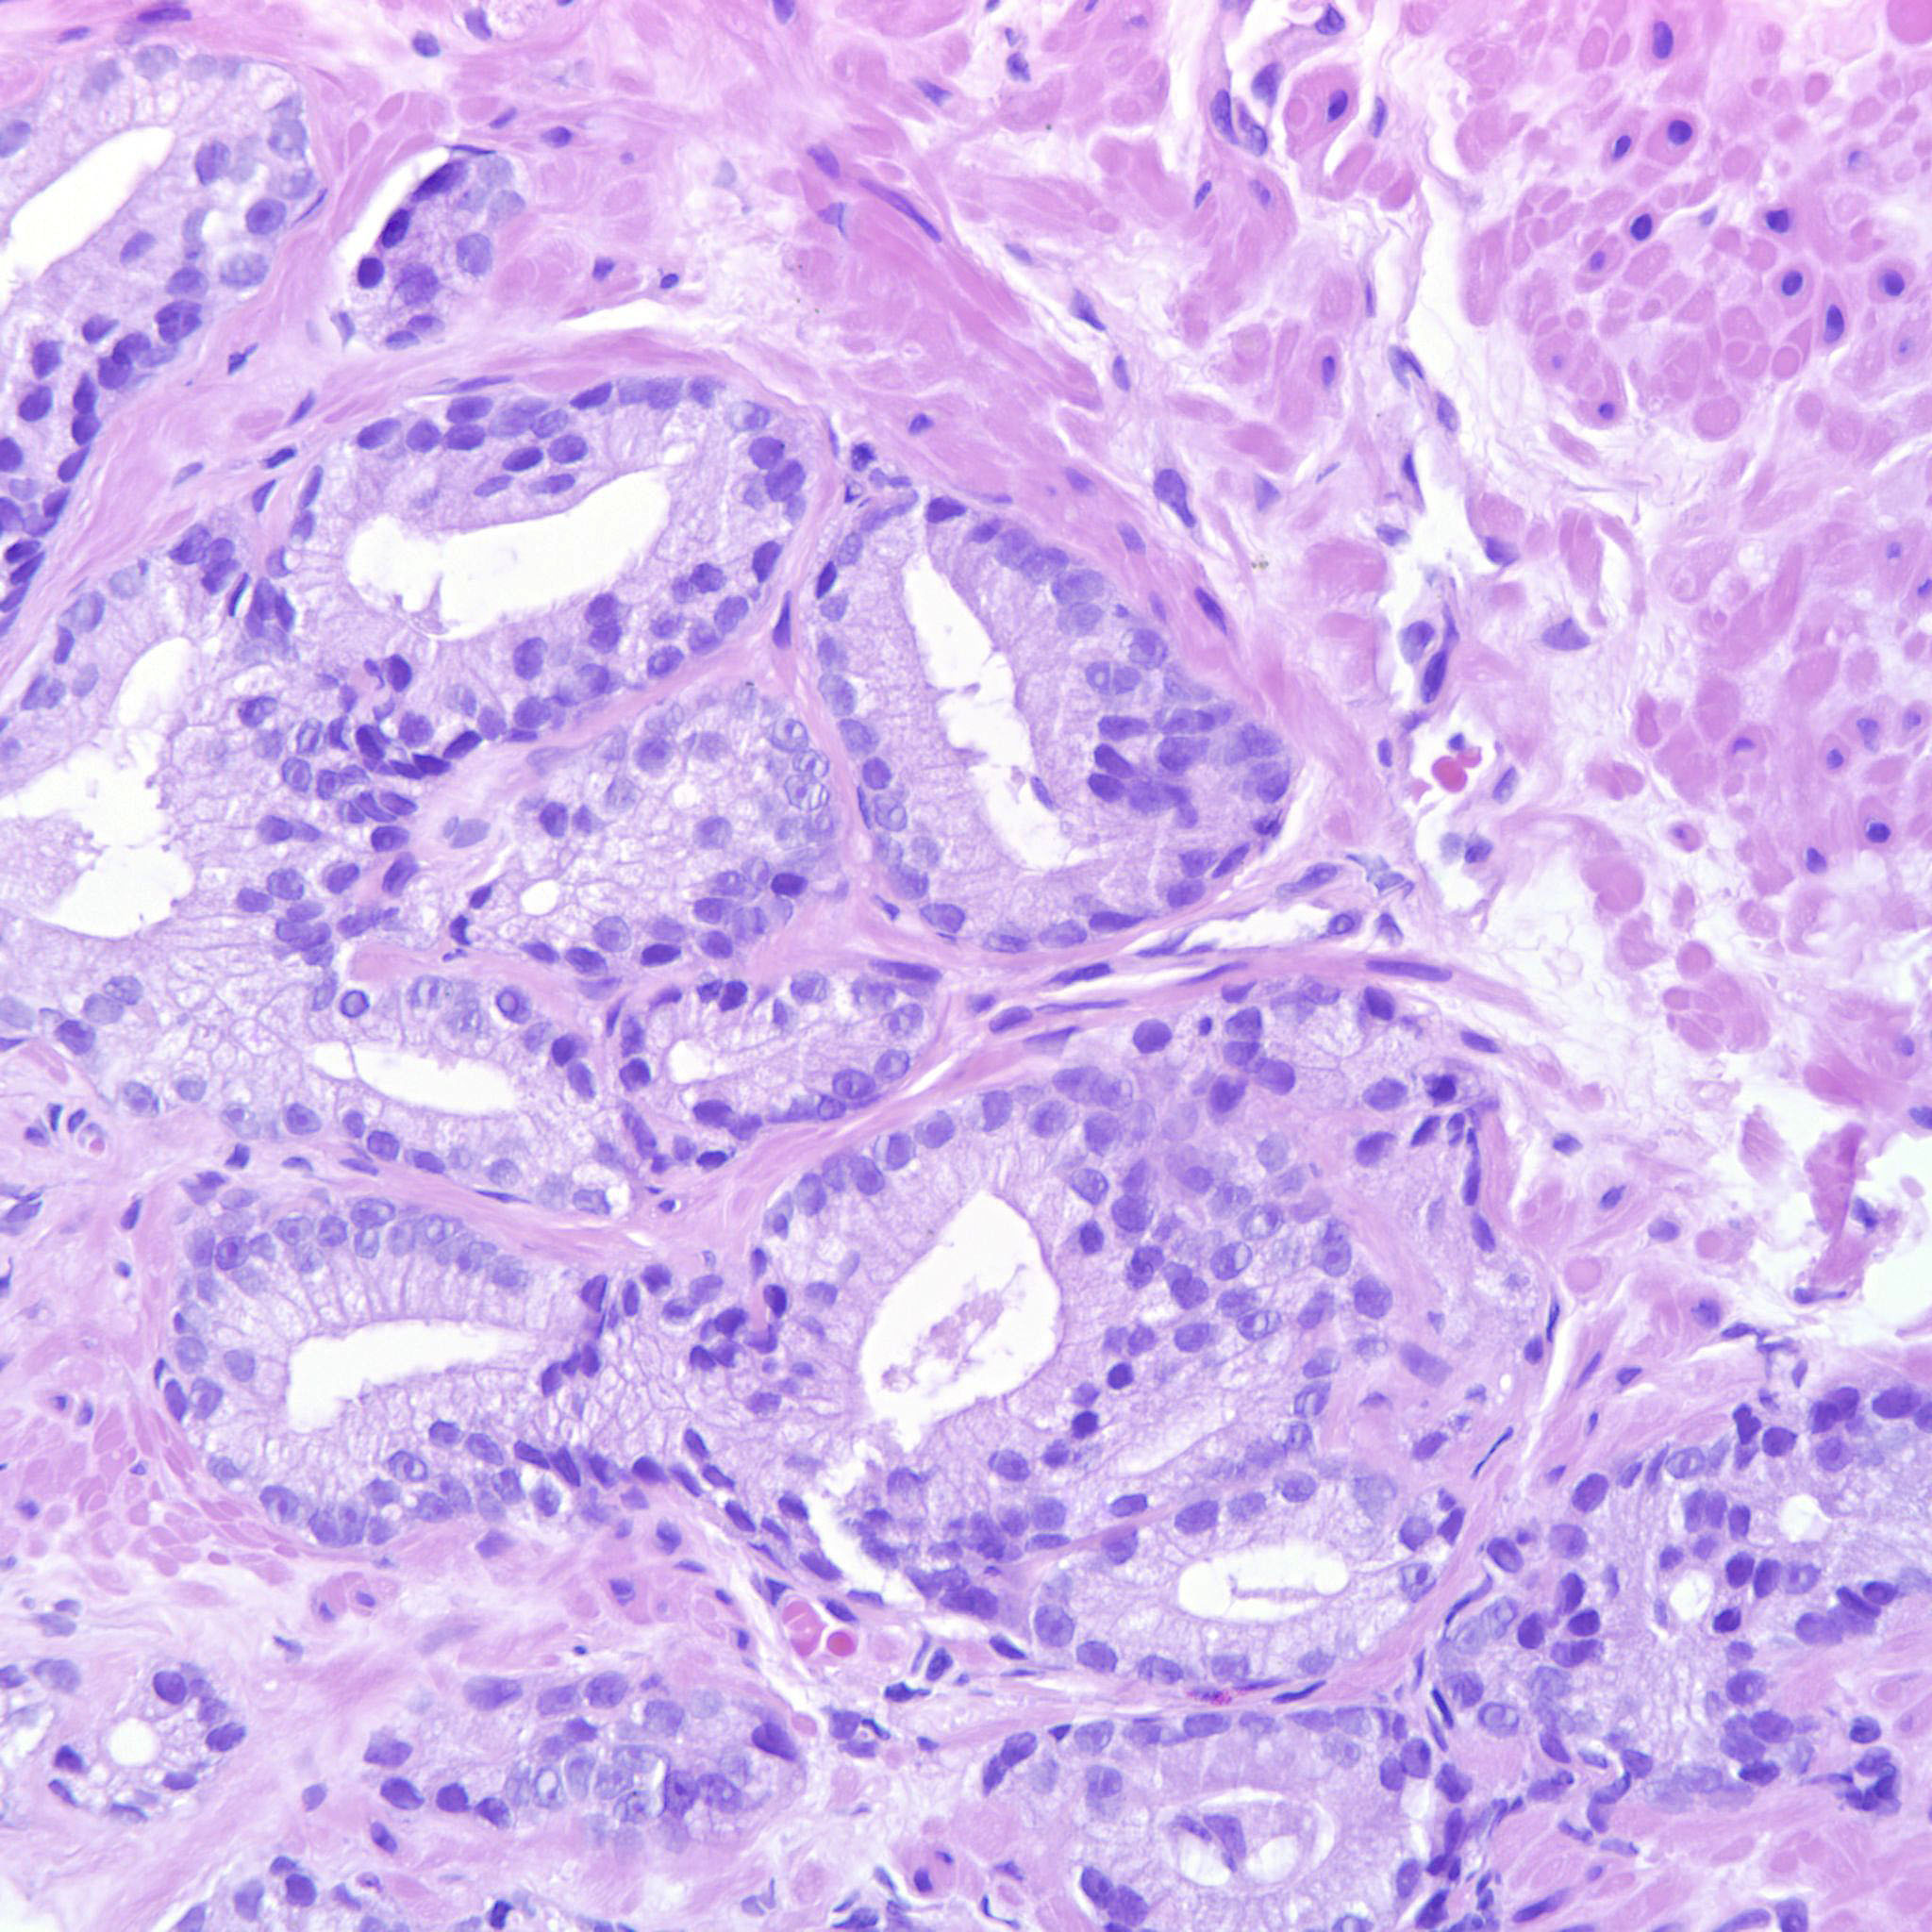

Prostate cancer grading

Case ID: 704